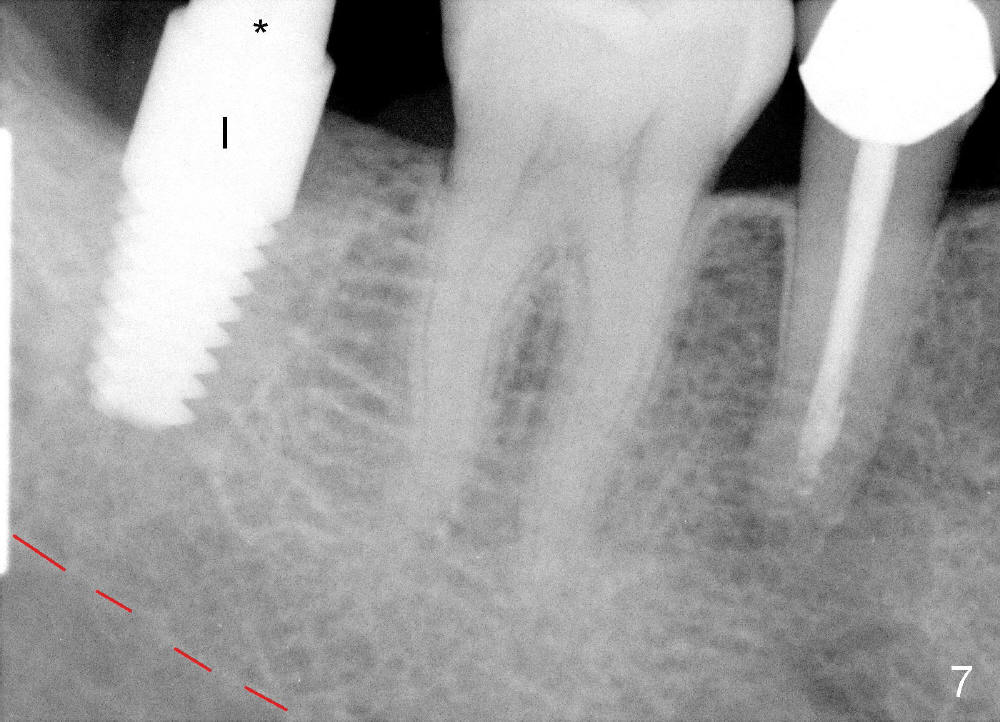

Infiltration anesthesia is administered with 68 mg of Septocaine, 34 mg of Lidocaine, 34 mcg of Epinephrine around the site of the lower right 2nd molar. An incision is made. A 2 mm pilot drill is used to initiate osteotomy at the depth of 8 mm. A parallel pin is inserted for the 1st intraop PA (Fig.4: P), which shows once more time the likelihood of incooperation from the patient. Combined with the information from CT, it appears alright to continue increasing osteotomy in the diameter and depth until 5x11 mm (Fig.5,6 (T: tap)). A 6x14 mm tap is inserted at 11 mm in bone. When the tap is removed, an explorer is used to check the intrigity of the osteotomy walls. No vibration is palpated linguoapically during drilling and inserting taps. There is no abnormal hemorrhage from the osteotomy. Finally 6x14 mm implant is placed as expected (Fig.7). The wound is healing 6 days postop (Fig.8).